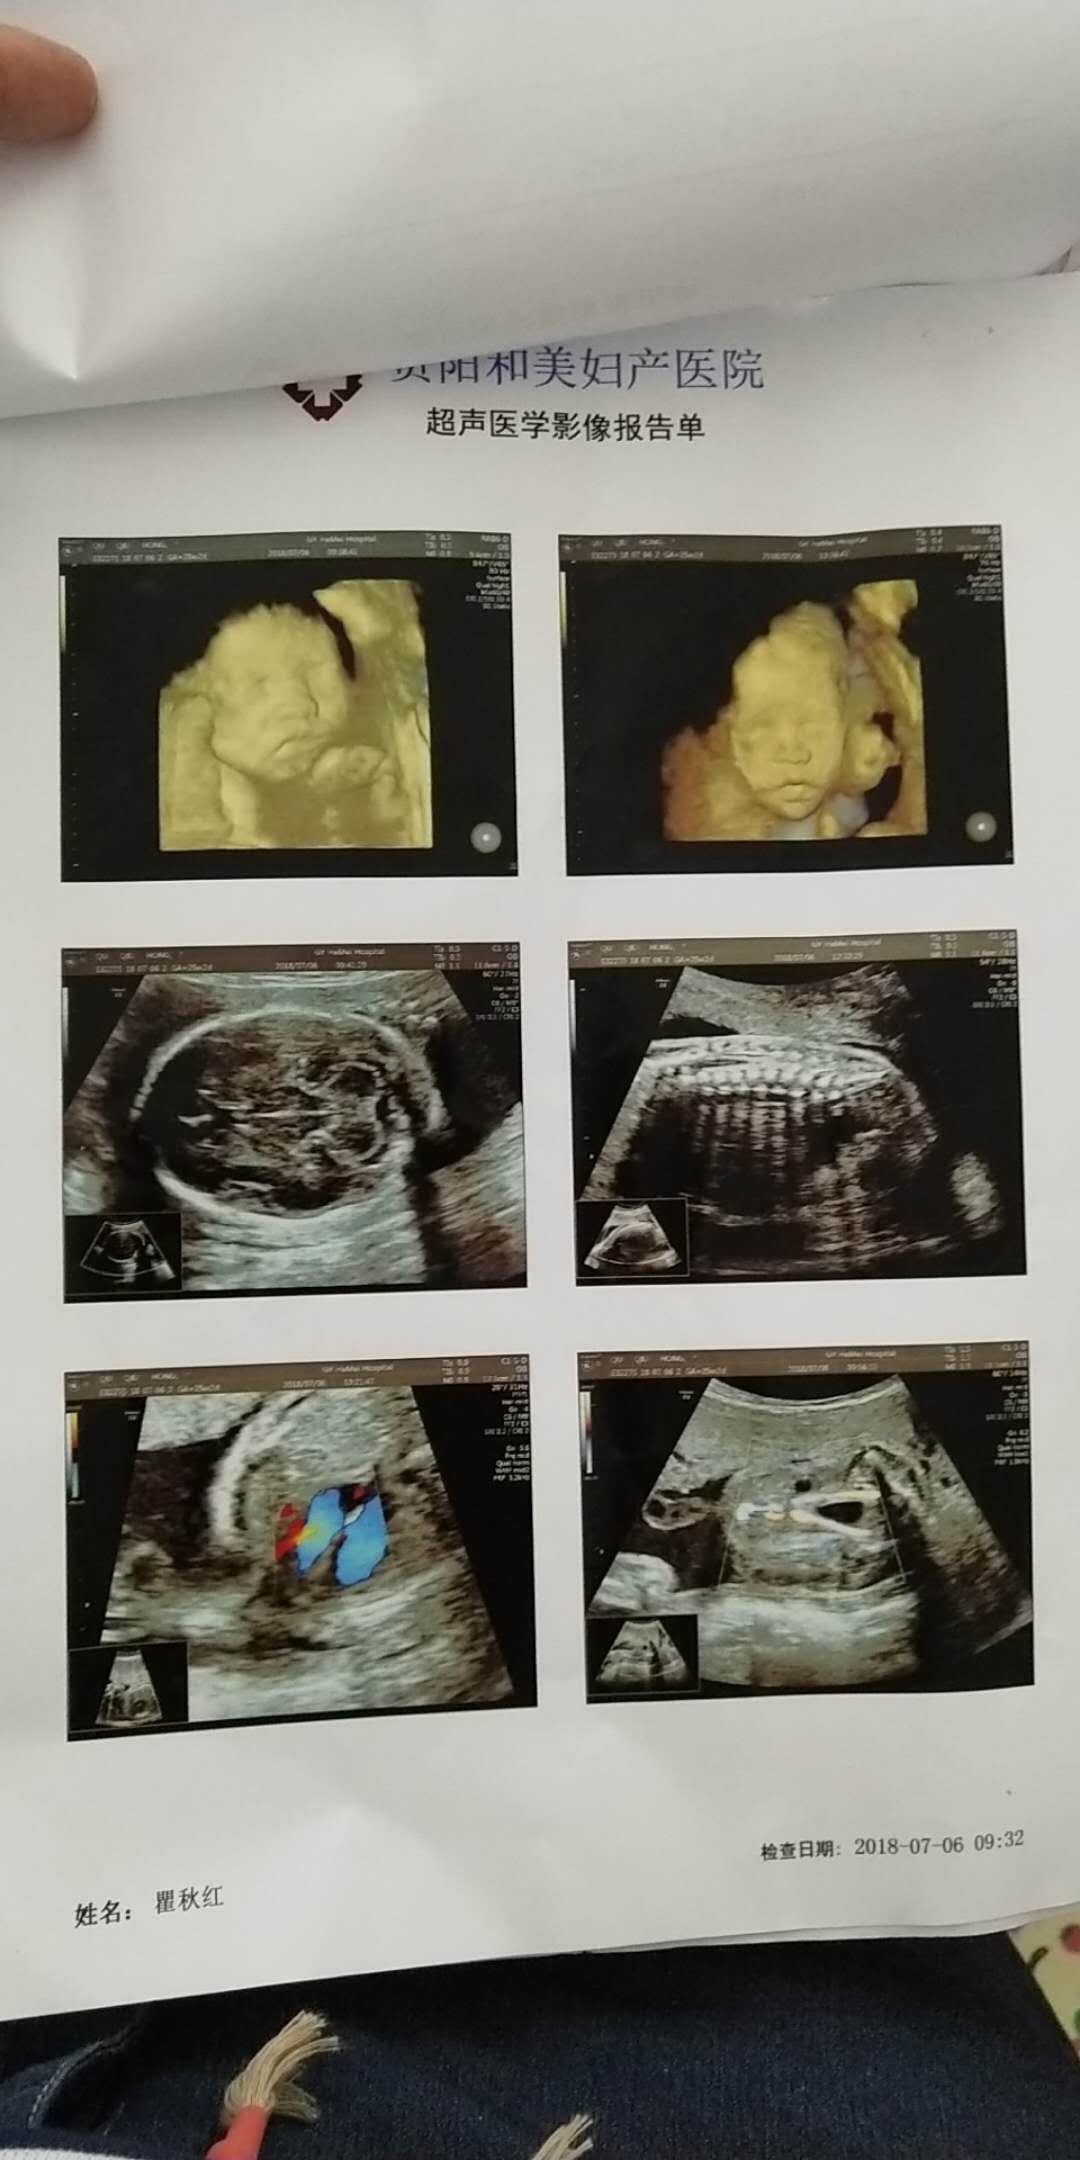

这个是系统B超吗?

踮起脚尖💋你[帖主]:四维彩超